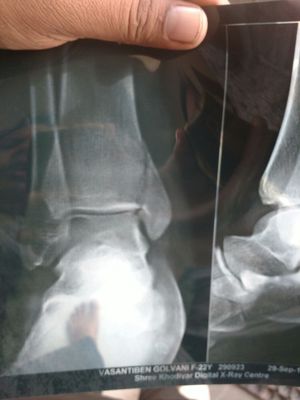

How to treat

Fracture

Xray

Bone